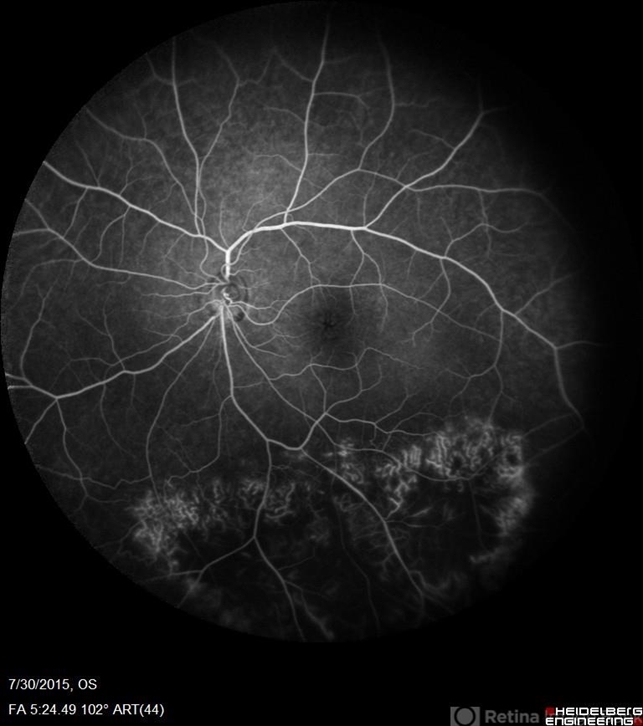

- Retinal Dystrophy of 24 Year Old Male

- retinal dystrophy, Goldmann-Favre Syndrome, juvenile retinoschisis

- Fluorescein angiography of a 24-year-old male. Juvenile retinoschisis on OCT. FA shows outer retinal staining. Could be associated with Goldman Farve Syndrome.